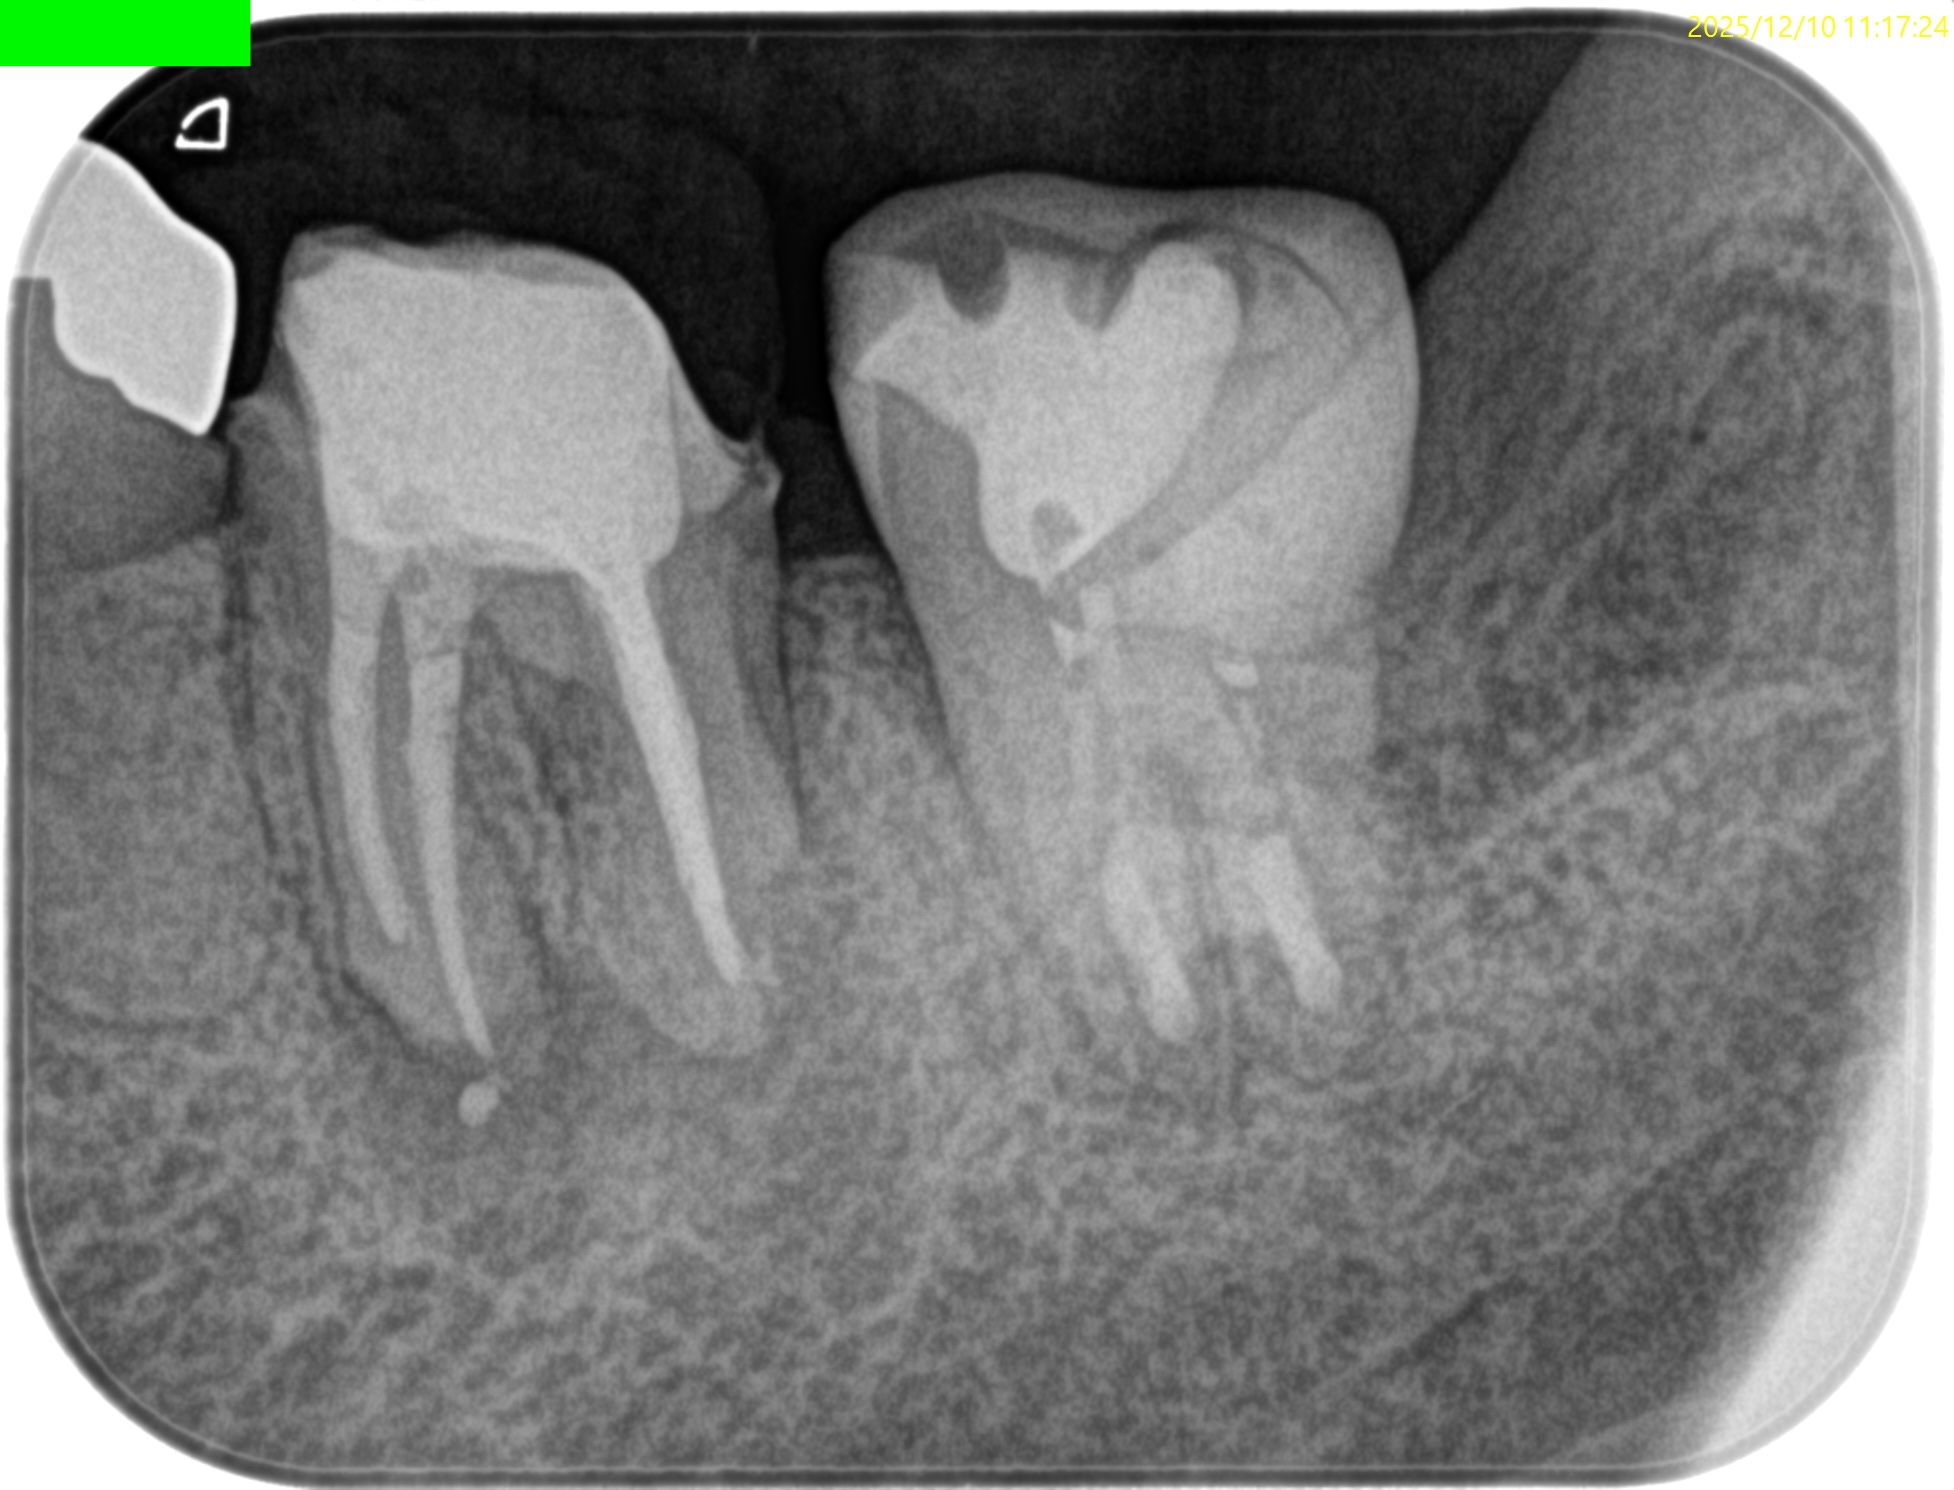

PAを撮影した。

歯牙を抜歯窩へ再植した。

咬合を最後に確認した。

PA, CBCTを撮影した。